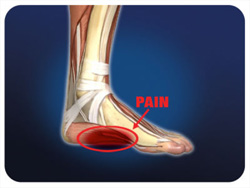

Ποια είναι τα συμπτώματα

Ο πόνος είναι το πιο συχνό σύμπτωμα και ενόχληση. Μπορεί να παρουσιαστεί σε οποιοδήποτε σημείο του πέλματος αλλά συνήθως υπάρχει ένα σημείο με μεγαλύτερη ευαισθησία, 3-4 εκατοστά πιο μπροστά από την πτέρνα και το οποίο μπορεί να είναι επώδυνο ακόμη και στην ψηλάφηση. Ο πόνος είναι μεγαλύτερος συνήθως στα πρώτα βήματα ή το πρωί που σηκωνόμαστε από το κρεβάτι και στη συνέχεια να υφίεται αλλά νασυνεχίζει να ενοχλεί. Πόνος εμφανίζεται επίσης μετά από πολύωρη βάδιση ή άθληση. Επίσης σε ξαφνική τάση του πέλματος όπως σε σκάλες ή όταν στεκόμαστε στα δάκτυλα των ποδιών μπορεί να αυξηθεί ο πόνος. Μπορεί οι ενοχλήσεις να είναι τόσο έντονες που να κουτσαίνουμε, ενώ σπανιότερα μπορεί να έχουμε τις ίδιες ενοχλήσεις και στα δύο πόδια.

Ο πόνος είναι το πιο συχνό σύμπτωμα και ενόχληση. Μπορεί να παρουσιαστεί σε οποιοδήποτε σημείο του πέλματος αλλά συνήθως υπάρχει ένα σημείο με μεγαλύτερη ευαισθησία, 3-4 εκατοστά πιο μπροστά από την πτέρνα και το οποίο μπορεί να είναι επώδυνο ακόμη και στην ψηλάφηση. Ο πόνος είναι μεγαλύτερος συνήθως στα πρώτα βήματα ή το πρωί που σηκωνόμαστε από το κρεβάτι και στη συνέχεια να υφίεται αλλά νασυνεχίζει να ενοχλεί. Πόνος εμφανίζεται επίσης μετά από πολύωρη βάδιση ή άθληση. Επίσης σε ξαφνική τάση του πέλματος όπως σε σκάλες ή όταν στεκόμαστε στα δάκτυλα των ποδιών μπορεί να αυξηθεί ο πόνος. Μπορεί οι ενοχλήσεις να είναι τόσο έντονες που να κουτσαίνουμε, ενώ σπανιότερα μπορεί να έχουμε τις ίδιες ενοχλήσεις και στα δύο πόδια.